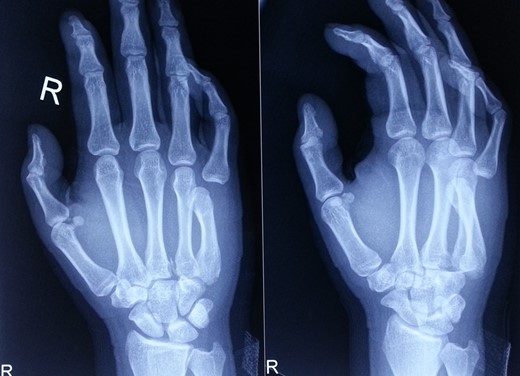

A 28-year-old gentleman presented to us with complaints of pain and swelling of the right hand for 2 hr. He sustained an injury to his hand when his motorbike skid and he landed on the ulnar aspect of his hand and little finger. On examination, there was swelling, tenderness and deformity on the ulnar aspect of his hand. There was restriction of movement of the fifth finger. His wrist movements were normal, and there were no open wounds in hand. Radiological evaluation revealed dorsal dislocation of fifth CMC joint and volar dislocation of distal MCP joint (Fig. 1). Based on clinico-radiological examination, diagnosis of close, fifth floating finger was made. Closed reduction of the dislocations was done under sedation in emergency room, and wrist splint supporting the head of MCs was applied. Immediate post-reduction stability of the joints was assessed and the joints were found to be stable. Post-reduction radiographs (antero-posterior and oblique views) confirmed the reduction of both CMC and MCP joints (Fig. 2). The splint was removed after 3 weeks, and finger and wrist range of motion (ROM) exercises were started. At 6 months follow-up, his finger and wrist ROM were full. Grip strength was comparable on both sides and his movements were pain free (Fig. 3). No abnormalities were detected on the radiographs at 6 months follow-up (Fig. 4).